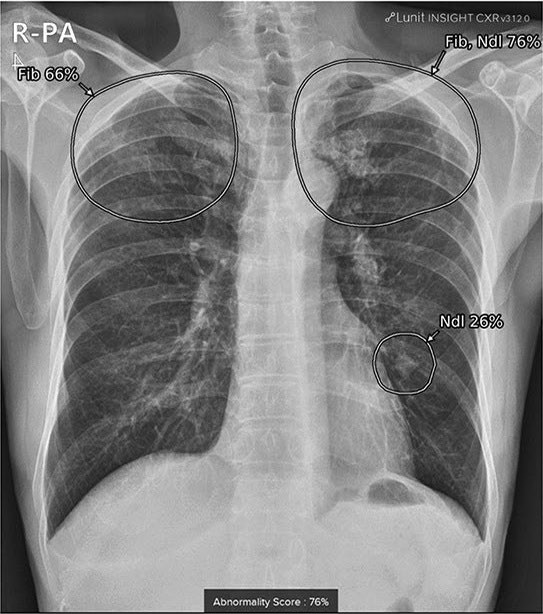

AI detects incidental lung nodules on chest xrays Radiology AI

AI improves lung nodule detection on chest Xrays What Are Nodules On Chest X Ray Lung nodules are small masses that grow inside the lungs. It’s rarely lung cancer, but you shouldn’t ignore it. They are found in up to half of adults. A ct scan gives a more detailed image and can show. Pulmonary nodules are small, rounded opacities within the pulmonary interstitium. Lung nodules often are discovered incidentally during imaging for other health.. What Are Nodules On Chest X Ray.

From radiologyai.com

AI detects incidental lung nodules on chest xrays Radiology AI What Are Nodules On Chest X Ray Pulmonary nodules are small, rounded opacities within the pulmonary interstitium. A lung nodule is a small mass of dense tissue on the lung. They are found in up to half of adults. Lung nodules are small masses that grow inside the lungs. A ct scan gives a more detailed image and can show. It’s rarely lung cancer, but you shouldn’t. What Are Nodules On Chest X Ray.